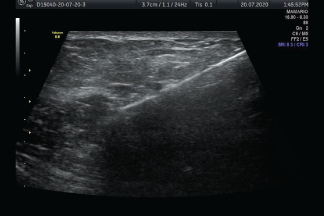

Una biopsia guiada por ultrasonido utiliza ondas sonoras para ayudar a localizar un bulto o anormalidad y extraer una muestra de tejido para examinarla bajo microscopio. Es menos invasiva que la biopsia quirúrgica, deja poco o nada de cicatriz, y no requiere de la exposición a la radiación ionizante.

La biopsia guiada por imágenes se realiza tomando muestras de una anomalía bajo alguna forma de guía, como ultrasonido, resonancia magnética o guía mamográfica.

Las imágenes por ultrasonido se utilizan para ayudar a guiar los instrumentos del radiólogo hasta el sitio del crecimiento anormal.